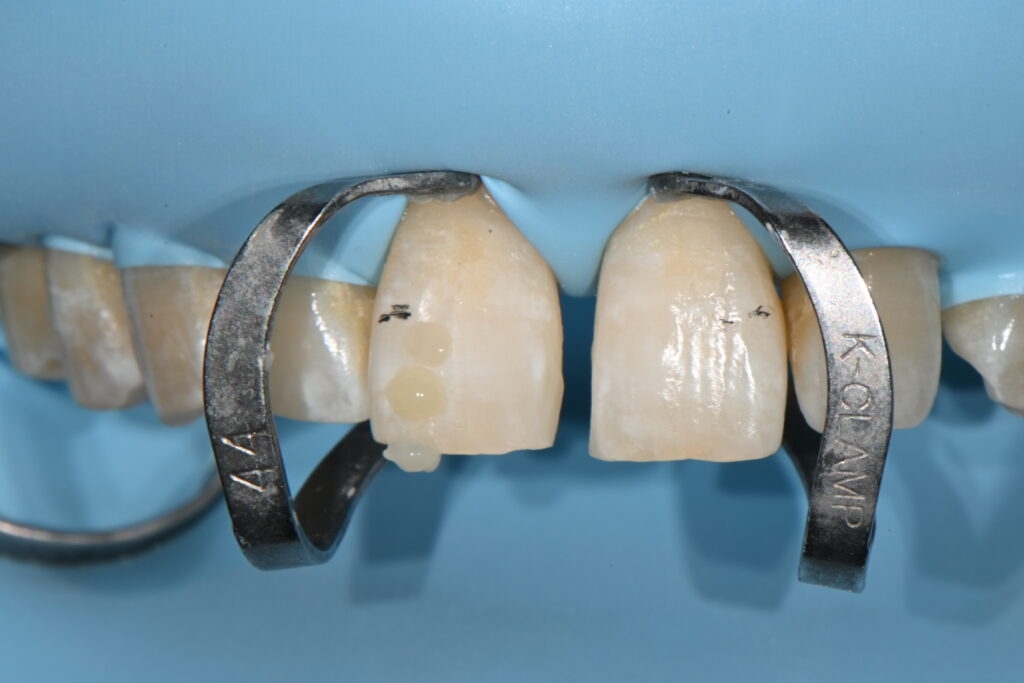

레진치료의 첫번째 조건 –완전한 방습으로 치료해야 합니다

방습을 시행하고 그리고 레진의 색상을 골라줍니다

레진은 다양한 색상이 있지만 사람의 치아는 그보다 더 다양한 색상을 가지고 있습니다

최대한 맞추어서 유사한 색상을 재현하는게 포인트이지요

그리고 치아의 형태를 잡아주는 바이오 클리어라는 재료가 필수입니다

이 재료가 나오고 나서 정말 레진치료가 좋아졌습니다

이렇게 형태를 잡아줄것으로 생각됩니다